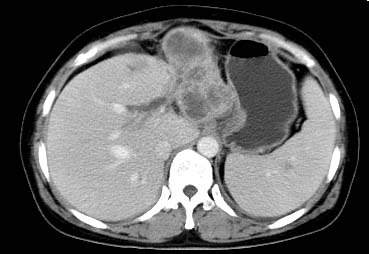

以下是引用西北一只狼在2008-6-30 20:58:00的发言:[br]肝左叶胆管细胞ca并肝门淋巴结转移、胰腺、胃小弯浸润

以下是引用ydx_74在2008-6-30 21:54:00的发言:[br]左叶胆管细胞ca并肝门淋巴结转移、胰腺、胃小弯浸润